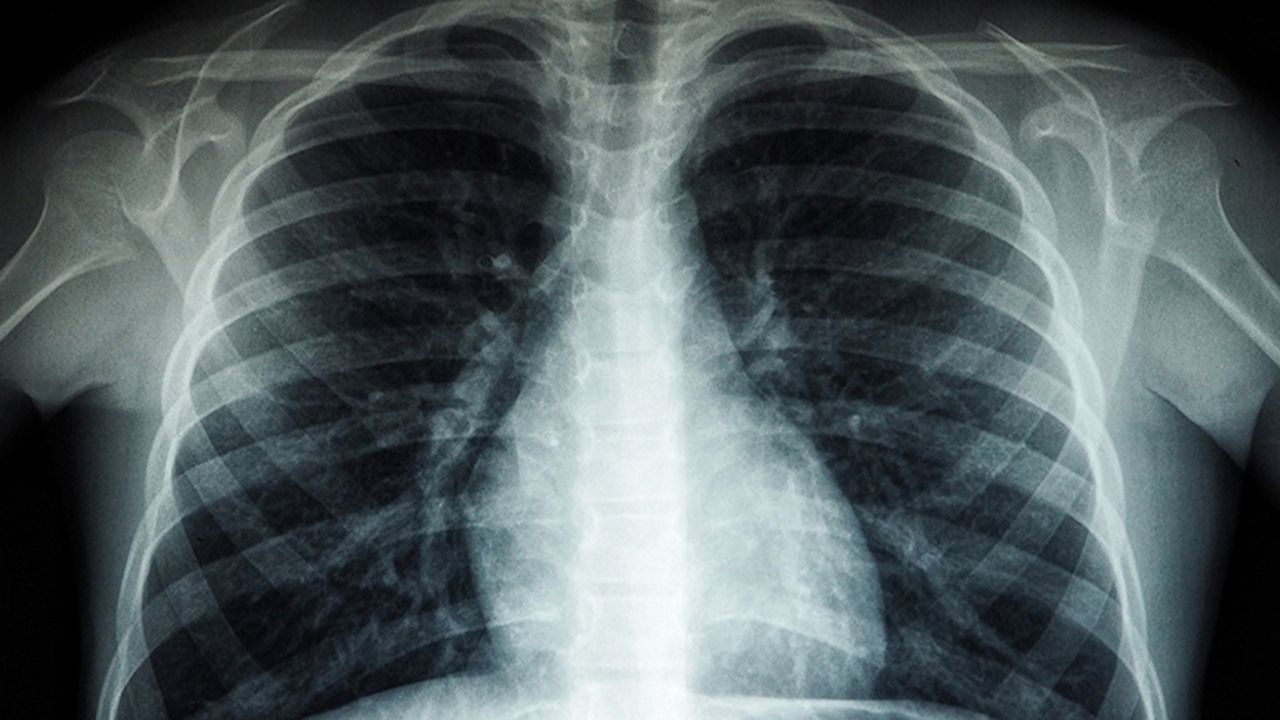

“Pnömoni; bakteriler, virüsler veya mantarların neden olduğu bir akciğer enfeksiyonudur. Özellikle risk gruplarında hayati tehlike oluşturabilir. Ancak düzenli hekim kontrolleri, aşılama ve sağlıklı yaşam alışkanlıklarıyla bu riski önemli ölçüde azaltmak mümkündür. Kronik hastalığı bulunan ve ileri yaşta olan vatandaşlarımızın sağlık taramalarını ihmal etmemeleri gerekiyor.”

Pnömoninin genellikle soğuk algınlığıyla karıştırıldığına dikkat çeken Doç. Dr. Bildirici, erken teşhisin hayati önem taşıdığını belirtti:

“Uzun süren öksürük, balgam, göğüs ağrısı, yüksek ateş, titreme, halsizlik ve nefes darlığı gibi şikayetler pnömoni habercisi olabilir. Bu belirtiler görüldüğünde zaman kaybetmeden bir sağlık kuruluşuna başvurulmalıdır. Erken teşhis, tedavi sürecinin başarısını belirleyen en önemli unsurdur.”